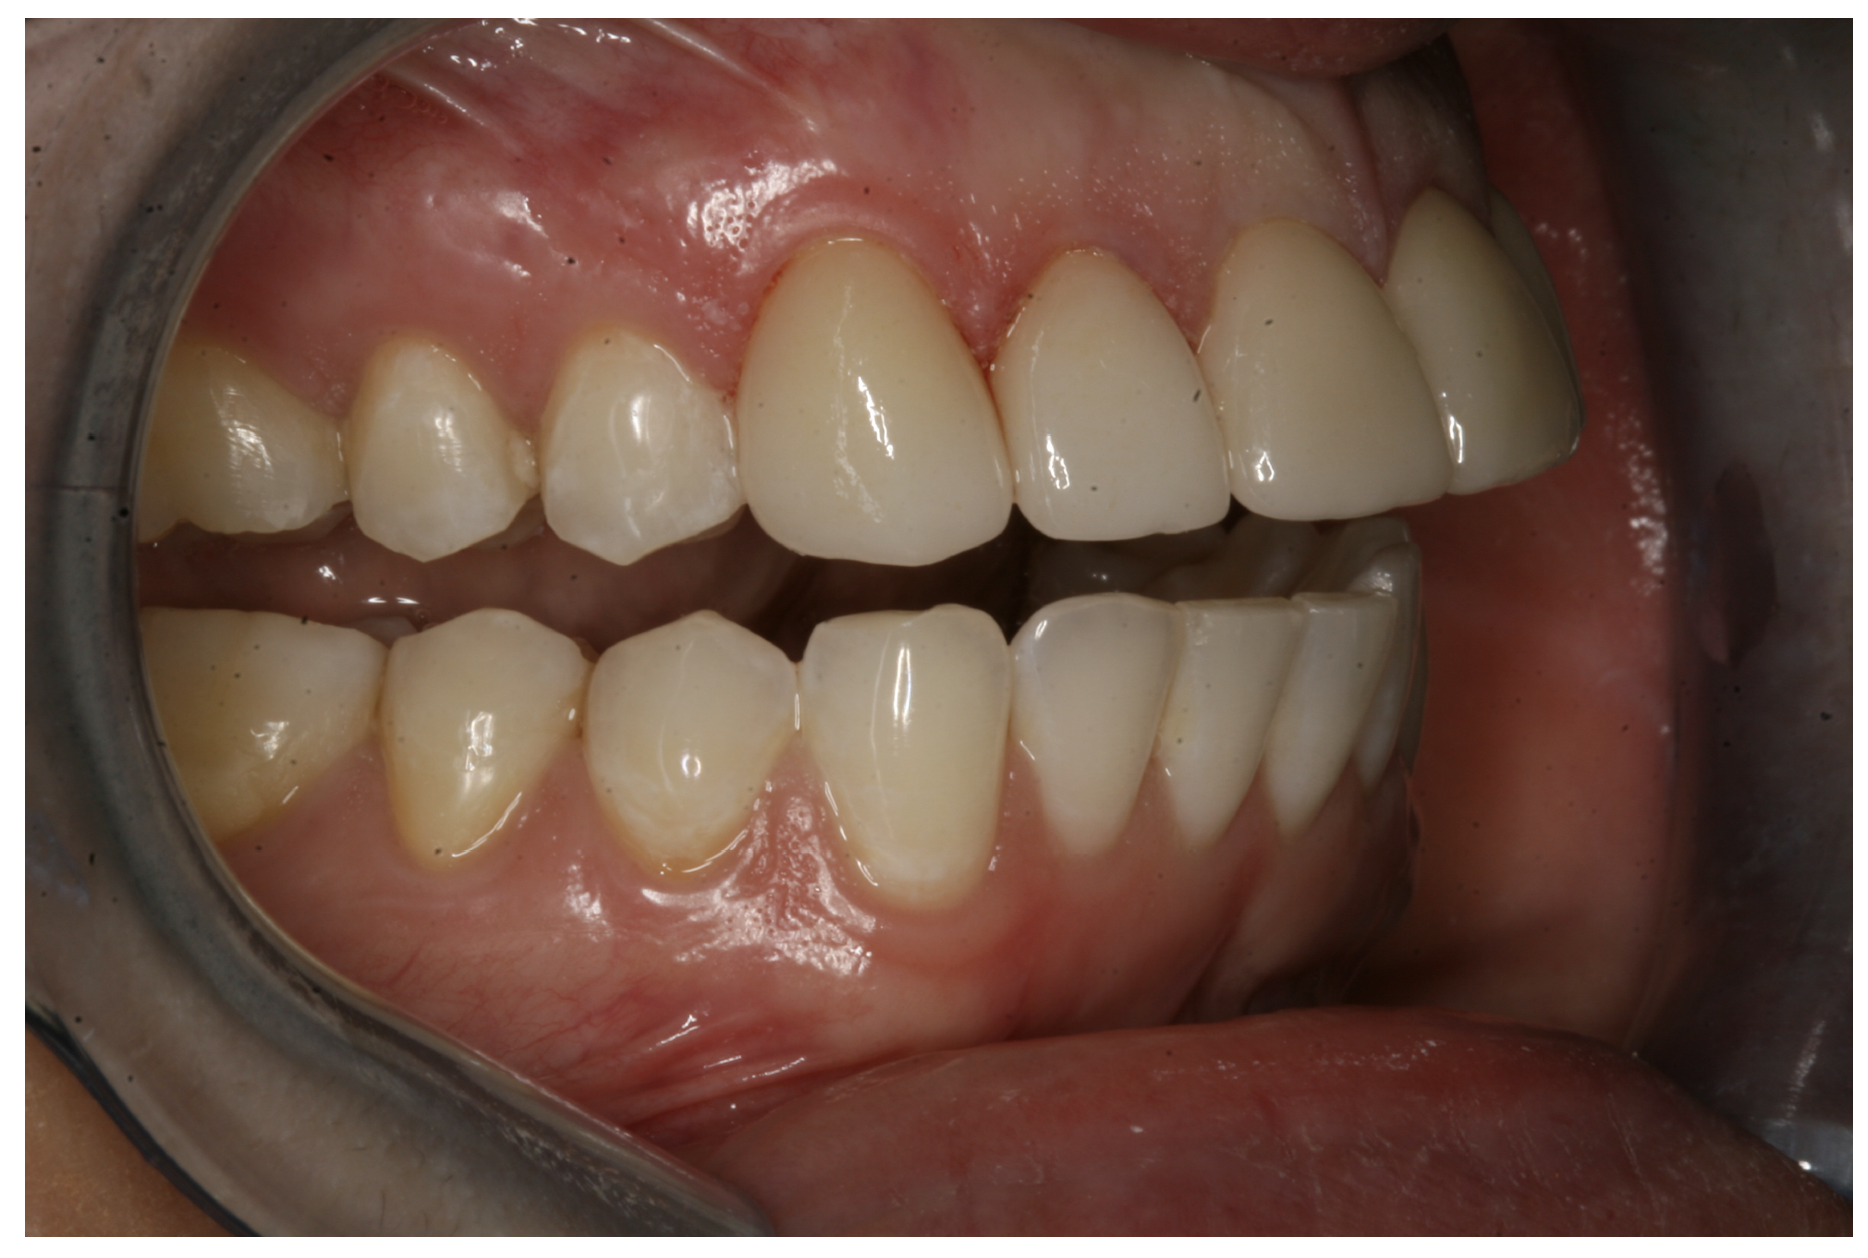

For the case in Figure 9 through Figure 11, the patent presented for an initial consultation with bonding completed on teeth Nos. 7 through 10 a few years prior with a chief complaint of not liking the way the resin bonding looked and how it was wearing. Up to this point, the bonding had repeatedly chipped and been repaired three times already. The patient's canines also exhibited signs of incised wear and flattening, which she did not like. Based on the patient's goals for her smile and her financial budget, she elected to have porcelain veneers completed on teeth Nos. 6 through 11. The total esthetics of the case design were somewhat limited given that the patient's esthetic zone included her posterior teeth and mandibular anterior teeth. Therefore, the color and characteristics of the veneers had to match her existing dentition closely.